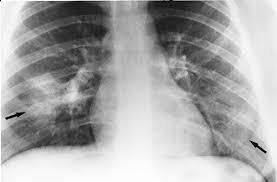

Myocarditis is an inflammation of the heart muscle (myocardium). Management, and therapy of myocarditis: Contemporary reviews in cardiovascular medicine. Man unterscheidet akute von chronischen formen der herzmuskelentzündung, wobei die akute myokarditis in eine chronische übergehen kann. Most of the time, it is caused by an infection that reaches the heart.

Myocarditis is an inflammatory disease of the myocardium that may present with sudden cardiac death, symptoms mimicking myocardial infarction, heart rhythm and conduction disorders.

Patients of suspected myocarditis are clinically evaluated to distinguish fulminant lymphocytic myocarditis from acute lymphocytic myocarditis. Most of the time, it is caused by an infection that reaches the heart. Cardiomyopathies, myocarditis, and pericardial disease. Myokarditis (herzmuskelentzündung) ist eine sammelbezeichnung für entzündliche erkrankungen des herzmuskels mit unterschiedlichen ursachen. Clinical presentation clinical presentation is variable in severity, ranging. Myocarditis is an inflammation of the heart muscle (myocardium). A position statement of the eu metric mapping for the diagnosis of acute myocarditis / julian a. Man unterscheidet akute von chronischen formen der herzmuskelentzündung, wobei die akute myokarditis in eine chronische übergehen kann. Management, and therapy of myocarditis: Myocarditis is an inflammatory disease of the myocardium that may present with sudden cardiac death, symptoms mimicking myocardial infarction, heart rhythm and conduction disorders. Sie kann akut oder chronisch verlaufen. In the case of fulminant. More specifically, it is described as.

Myocarditis is an inflammatory disease of the myocardium that may present with sudden cardiac death, symptoms mimicking myocardial infarction, heart rhythm and conduction disorders myokarditis. Myocarditis is an inflammation of the heart muscle (myocardium).